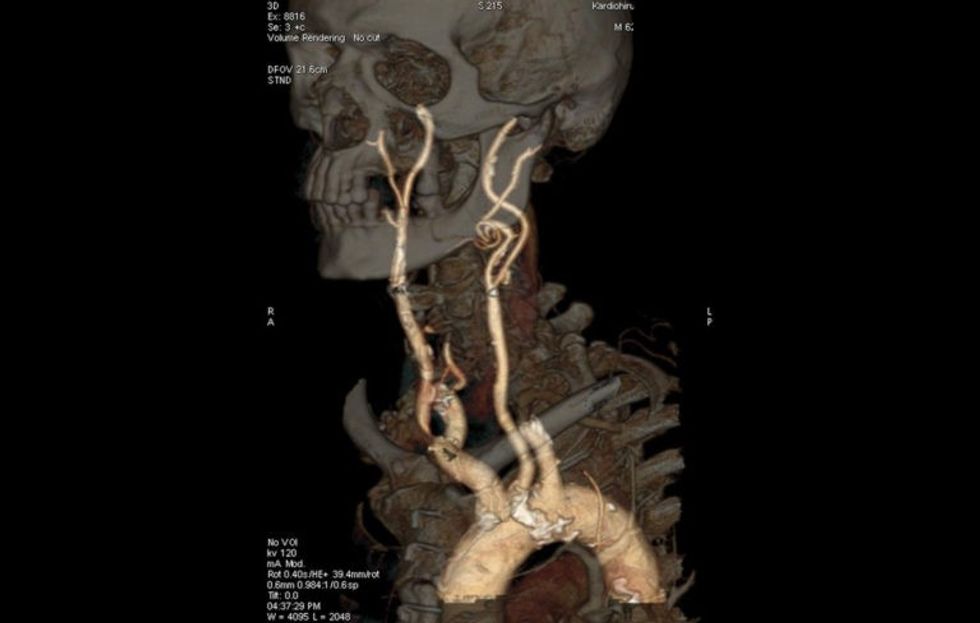

Dr. Idoski: Kardiologu juaj me kujdes do t'ju dëgjojë ankesat tuaja, do t'ju bëjë EKG dhe ekokardiografi, ky është ekzaminimi bazë. Nëse vërtetohet se kjo është sëmundja më e shpeshtë kardiovaskulare - sëmundja koronare, dmth bllokimi i enëve të gjakut që ushqejnë zemrën, kardiologu juaj do t'ju sugjerojë ekzaminime të mëtejshme si koronarografia - standardi i artë për diagnostikimin e sëmundjeve koronare të zemrës. Në Spitalin Klinik "Zhan Mitrev" ka dy mënyra për të kryer koronarografi: njëra është me ndihmën e metodës minimale invazive - imazhe kompjuterike me seksione 256 shtresash që shikojnë enët e gjakut që ushqejnë zemrën, ose me koronarografi klasike me një kateter. Për të dy ekzaminimet, qëndrimi në spital është 3-4 orë. Nëse gjatë regjistrimit zbulohet bllokim i enëve të gjakut në zemër, ekzistojnë tre mënyra për të zgjidhur sëmundjen:

Dr. Idoski: Studimet e fundit tregojnë se goditjet në tru dhe gangrena në këmbë janë më të shpeshta në pranverë. Nëse simptomat dhe ekografia tregojnë rrezik për goditje në tru për shkak të bllokimit të enëve të gjakut që ushqejnë trurin ose gangrenë për shkak të bllokimit të arterieve në këmbë, atëherë rekomandohet MSCT me 256 shtresa të atyre enëve të gjakut dhe nëse sëmundja është e avancuar përsëri në konsultimi me akademikun Dr. Zhan Mitrev do të bëhet operacion për të shpëtuar trurin ose këmbët. Ndërsa pacienti do të jetë në gjendje të kthehet në shtëpi për dy ose tre ditë dhe ngadalë të fillojë të kryejë përgjegjësitë e përditshme të punës. Në këtë mënyrë ndjeshëm ulet invaliditeti dhe mungesa në punë.